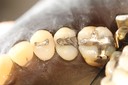

Photos of Clinical Operations

Drs. Peter Kearney, Terry McKay, John St. Germain, and Laurie Vanzella - Mentors